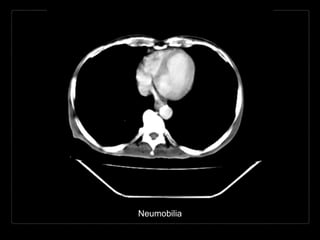

NEUMOBILIA

en el árbol biliar.

Hallazgos por imagen

• ramificaciones lineales de aire en el hígado

• más prominente en los conductos de mayor calibre

• central

• gas en el sistema venoso portal*

• ramificaciones de aire de calibre pequeño hacia la

periferia

NEUMOBILIA Acumulación de aire enel árbol biliar. Aerobilia

Hallazgos por imagen •ramificaciones lineales de aire en el hígado • más prominente en los conductos de mayor calibre • central • gas en el sistema venoso portal* • ramificaciones de aire de calibre pequeño hacia la periferia